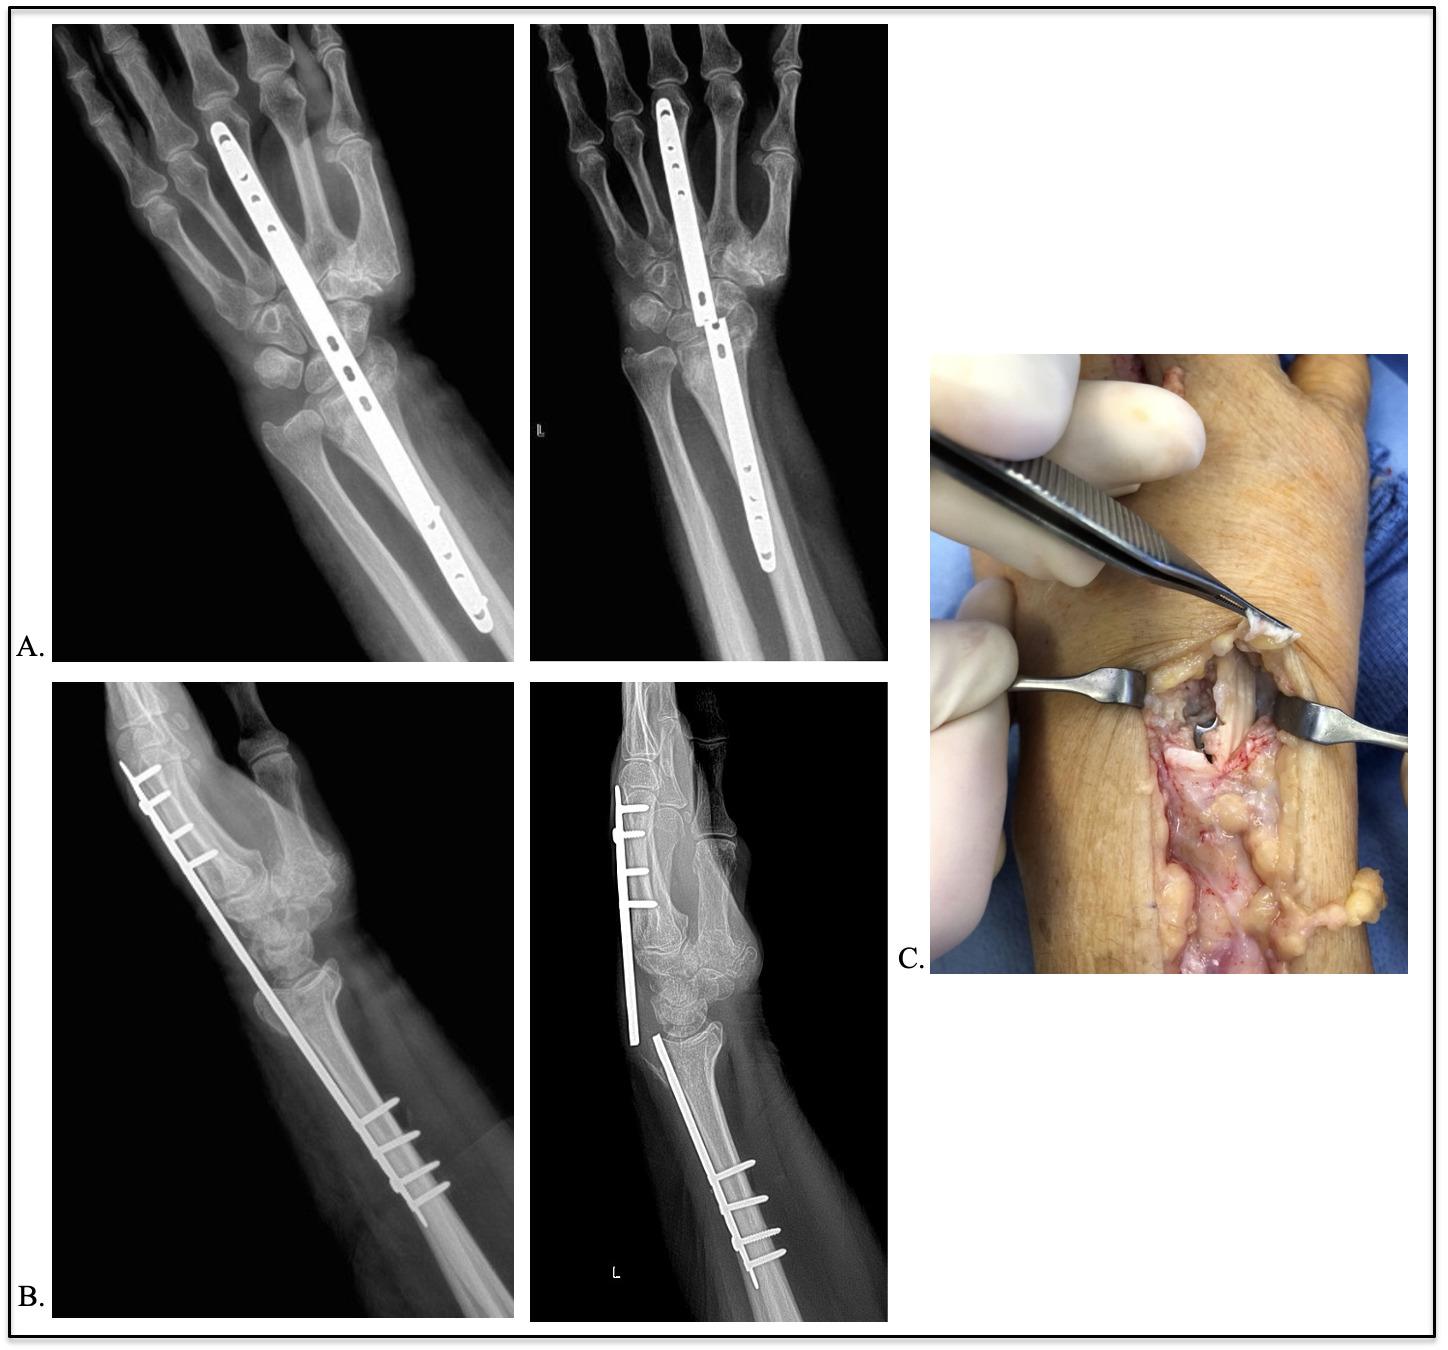

The surgery proceeded uneventfully. As intended, immediate weight-bearing through the repaired left wrist was allowed using a standard walker. Staged hardware removal was scheduled for 12 weeks postoperatively. However, at nine weeks postoperatively, the patient presented with acute onset wrist pain/swelling with increased motion and inability to extend her thumb. Of note, the patient previously had normal finger/thumb extension immediately post-operatively. Radiographs identified a fatigue fracture of the bridge plate through the central screw holes at the level of the wrist joint [Figure 2].

The patient received immediate surgical hardware removal and tendon repair. Satisfactory fracture healing was confirmed during this second surgery, with no additional internal fixation applied. Additionally, midsubstance rupture of the extensor pollicis longus tendon at the level of the plate’s fracture was confirmed and repaired with an extensor indicis proprius to EPL tendon transfer with no intraoperative complications [Figure 2]. Afterward, she was allowed to continue weight-bearing through the injured wrist and began tendon transfer rehabilitation immediately. The patient remained walker-dependent. No additional wrist intervention was required, with the last follow-up being approximately 13 months after the index surgery.